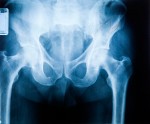

Greg Vigna, MD, JD, an academic rehabilitation physician serving a Level 1 Trauma Center in Indianapolis states, “Removable Inferior Vena Cava Filters (IVC) that are placed in traumatic brain injury, spinal cord injury and complex pelvic fracture patients are rarely removed within the FDA recommended time frame. The FDA states these filters should be removed between 29 to 54 days after placement; however, because of the very nature of the at risk population for which they are indicated, this doesn’t happen.”

Dr. Vigna, also an Academic Physician Life Care Planner, states, “There is a significant design defect with IVCs. These devices can fracture, migrate, puncture, and tilt, especially when they are used longer than two months. Filters remain in place longer than 54 days in over 90% of patients for a variety of reasons. Seeing patients on a daily basic with traumatic brain injury, spinal cord injury, and multiple fractures it is exceptionally rare that there is consideration to remove the device prior to 54 days. They remain at risk of falls that is a relative contraindication to anticoagulation, they have impaired mobility putting them at risk for blood clots, and often have future planned surgeries ahead that would prevent anticoagulation. Also, filters have been within the standard of care for over 25 years and severe complications related to the device are exceptionally rare so there is rarely a compelling reason to remove the device early”.